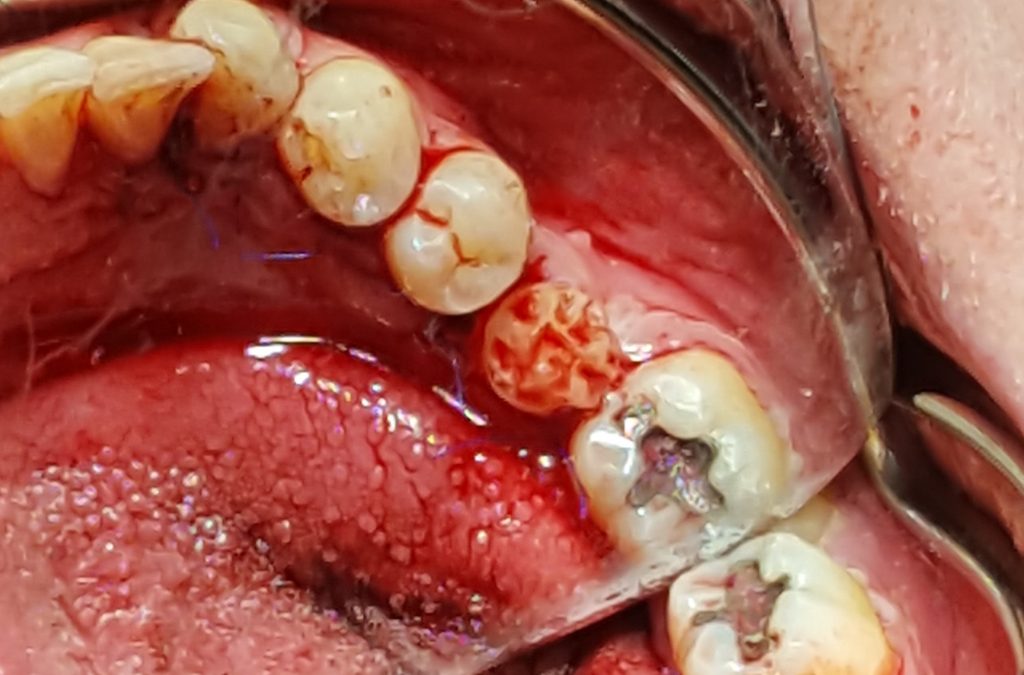

Autotransplantacja dodatkowego zęba 34 – opis przypadku

Title: Autotransplantation of an additional tooth 34 – a case report

Streszczenie: Autotransplantacja jest to przeszczepienie narządów w obrębie tego samego organizmu. Przeszczepianie zębów pacjenta w inne położenie jest metodą uzupełniania braków zębowych, która cechuje się dużym odsetkiem powodzenia. Zabieg ten stosuje się zarówno w przypadku zębów dojrzałych, jak i w zębach z niezakończonym rozwojem wierzchołka korzenia. Metoda ta w szczególnych przypadkach może być alternatywą dla leczenia implantoprotetycznego.

Summary: By definition, autograft is the transplantation of organs within the same organism. Transplanting a patient’s teeth in a different location is a method of filling missing teeth which is characterized by a high success rate. This treatment is used both for mature teeth and for teeth with the incomplete development of the apex of the root. The method can be an alternative for implantoprosthetic treatment.